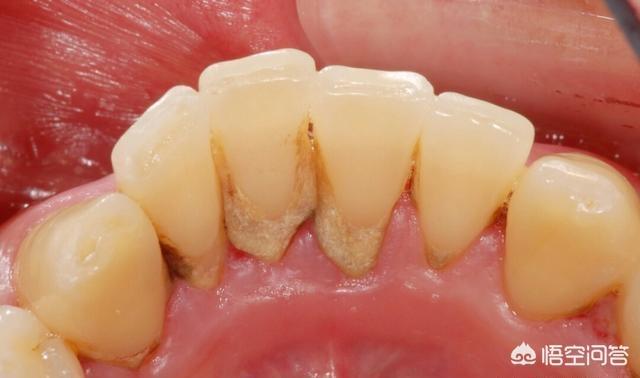

摘要:一般在医院洗牙100~500,牙结石较多,洗的时间也久,都会贵一些,另外私人诊所收费也不同,其实洗牙相当于给每颗牙齿洗一次澡,主要是震碎龈上的牙结石,包括牙缝都能冲洗干净,

一般在医院洗牙100~500,牙结石较多,洗的时间也久,都会贵一些,另外私人诊所收费也不同,其实洗牙相当于给每颗牙齿洗一次澡,主要是震碎龈上的牙结石,包括牙缝都能冲洗干净,你这种很可能是牙周炎,说明牙龈内还有残留物,具体得测牙周袋深度。

1、因为你洗晚了,牙结石多到占领你的牙缝,原本就被撑开了,而且牙龈肿胀,洗完炎症消退,自然就会呈现被破坏后的状态,并不是洗牙导致的,牙结石还会让牙槽骨吸收,牙齿松动,当演变成慢性炎症,严重牙齿将脱落。

2、想要让牙缝变小,就得先控制牙周炎,洗牙只是第一步,虽说不能治愈,但起码也是牙周基础治疗,牙周袋较深还得局部麻醉,进行龈下刮治,才能彻底清除牙结石,如果还未好转得牙周翻瓣手术,恢复稳定后,可以正畸关闭缝隙。